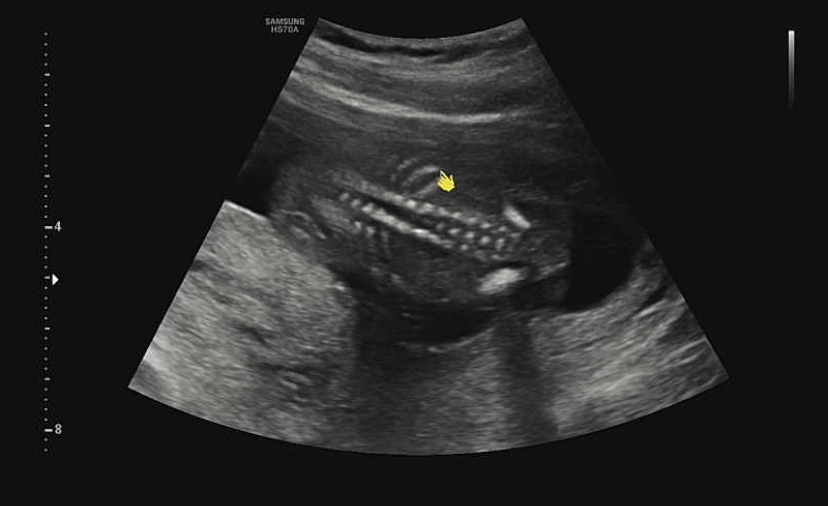

음..등뼈도 너무 잘 형성되었네(?) 초음파를 볼때마다 과학의 온라인 강의를 보는 느낌이다. 하나하나 새로운 것을 배워가는 것 같지만 감동적이고 사랑스러운 마음은 별로 들지 않는다! ^….